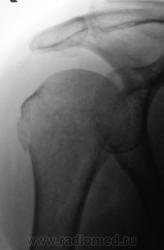

Травма.   Пациентка направлена на рентгенографию плечевого сустава.

Давно любимый вколоченный перелом х/шейки.